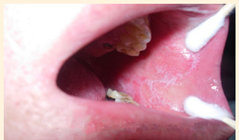

患者陈某,女,60岁,广东省深圳市人,患口腔扁平苔藓,自述口腔扁平苔藓多年,多方反复治疗无效,故来我院就诊。检查:右颊粘膜大面积红,表面有许多网状白膜。左颊大面积粘膜红,下部一块红溃烂,表面有白膜。经治疗10天红已减轻,经治疗4个疗程,双颊红溃已消除,但是表面还有少许白膜,经治疗第5个疗程时,白膜已消除,基本恢复正常。

陈某治疗前

陈某治疗后